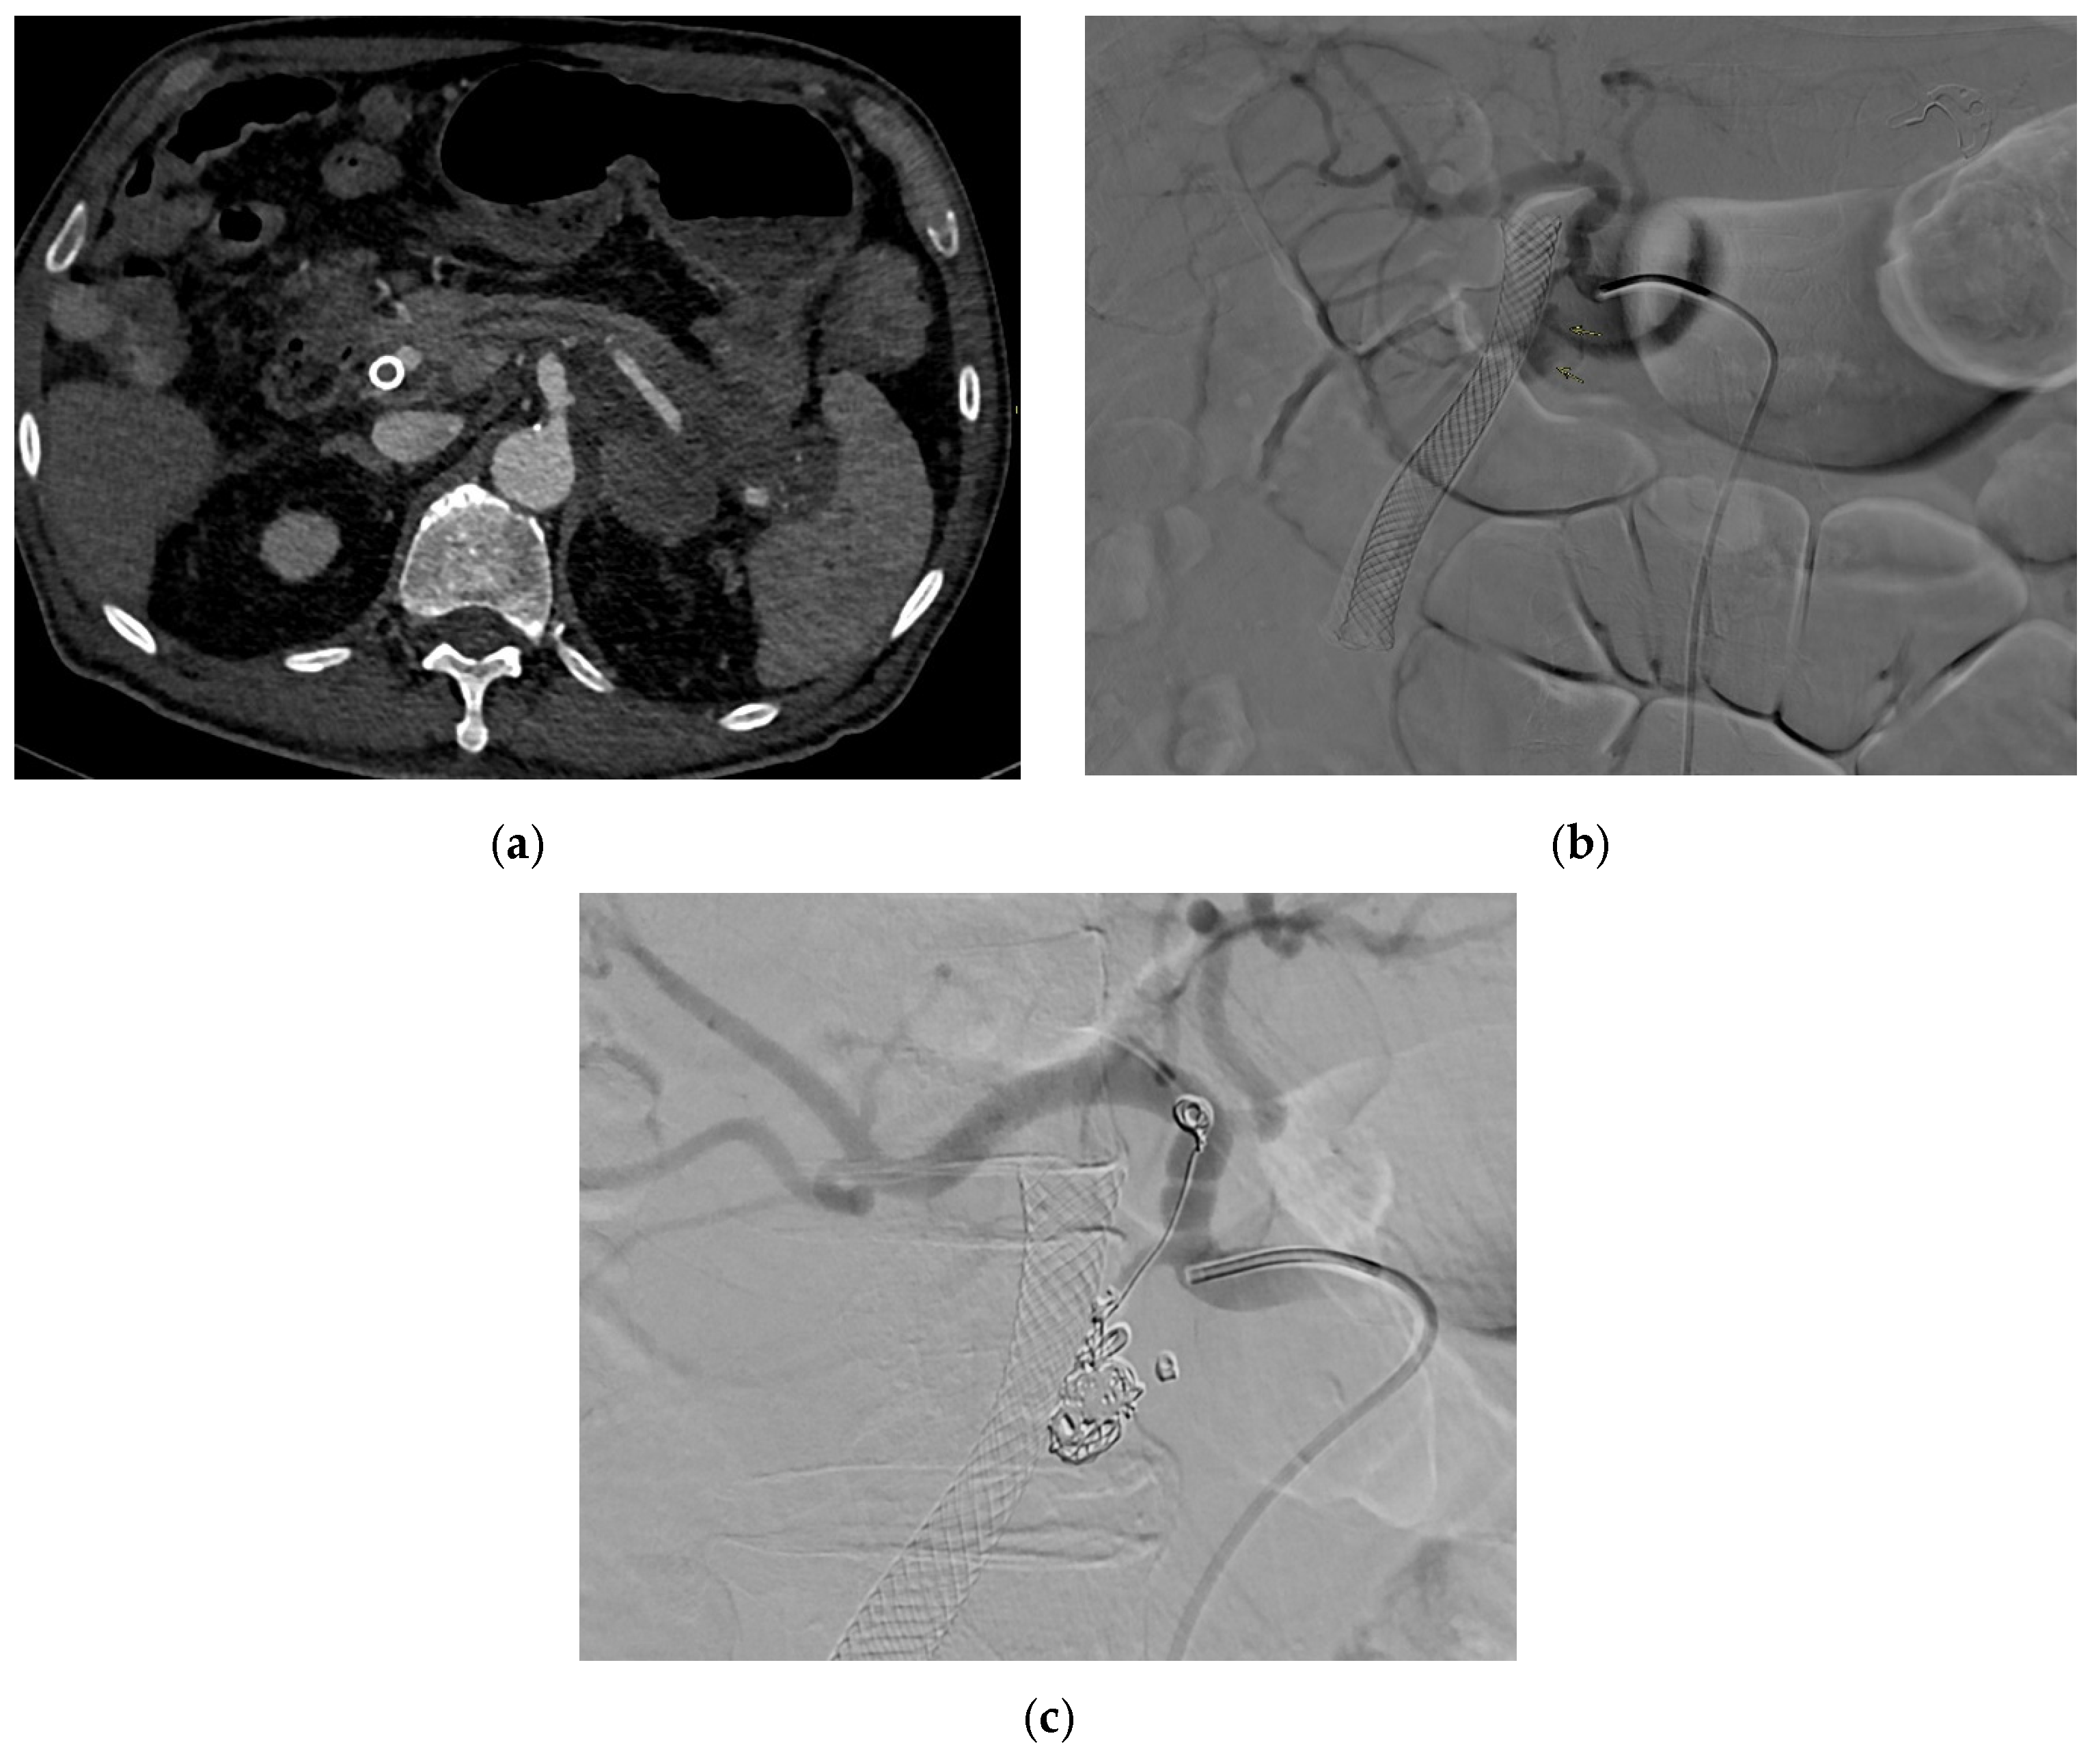

2.4. Splenic Artery

2.4.4. Diagnosis

2.4.5. Management

3.1.5. Management